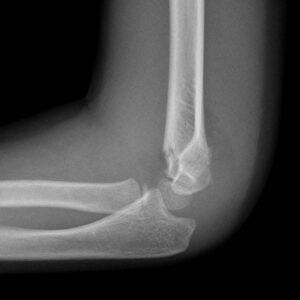

[toggle title=”Ön ve Arka Yağ Yastıkçığı Bulgusu” state=”close”]

Normalde eklem kapsülünde yağ yastıkçıkları bulunur.

Anterior yağ yastıkçığı koronoid fossada bulunur ve normal grafide de ince bir çizgi halinde görülebilir. Ancak anterior yağ yastıkçığı ayrışmış ve daha belirginleşmişse buna Yelken Bulgusu (Sail sign) denir ve görülmesi patolojiktir.

Olekranon fossada bulunan posterior yağ yastıkçığının grafide görülmesi ise her zaman patolojiktir.

Bazı non-deplase kırıklarda kırık hattı görülemeyebilir ve anormal yağ yastıkçığı işareti yaralanmanın tek bulgusu olabilir.

Travma öyküsü olan hastalarda yağ yastıkçığı görülmesi aksi kanıtlanana kadar kırığa sekonder düşünülmelidir.